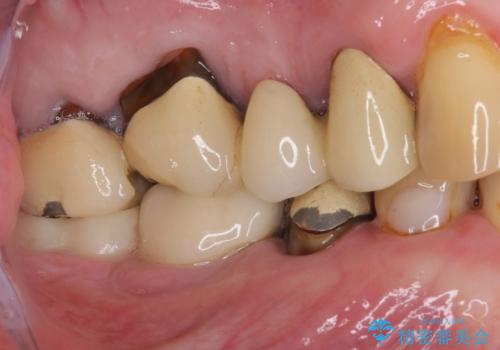

- 強い咬合力により表面のセラミックが剥がれ、裏打ちの金属が見えてしまっていることを気にして来院された患者様です。

仮歯に変えた後、咬合力に耐えることを目的に強化セラミッククラウンにて補綴することとしました。